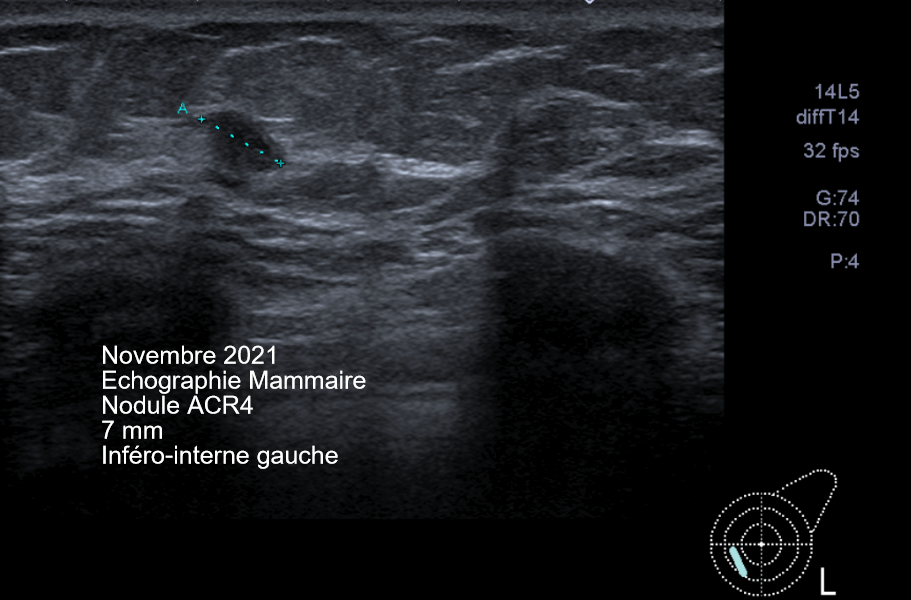

In November 2021, a new screening exam was performed.

The MammoScreen Score™ increased from 3 to 7 due to the appearance of a 7mm in the left breast.

The ultrasound confirms an atypical left 6.9 mm inferior-internal nodule that was the subject of an echo guided biopsy.

Histological examination confirmed infiltrating ductal carcinoma grade I, RO+, RP-, Ki-67 15%, HER2 score -, luminal phenotype B.